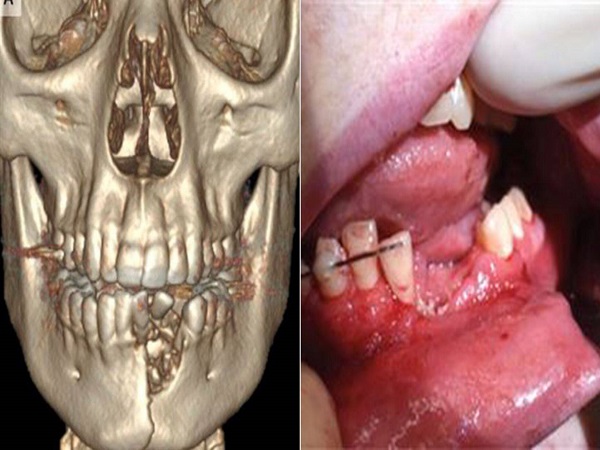

The doctors had to remove some of his teeth and the damaged tissue. Since the damage was so severe, they had to even construct a mandibular maxillary fixation in his mouth. The boy has apparently recovered in a six-week span.

The 17-year-old teen insisted his mum on gifting him with a vape pen as he was keen on giving up on smoking. Unfortunately, he was left with injuries which looked like "close-range gunshot wounds." The injuries were caused after a vape pen exploded in his mouth.

His injuries were so severe that he had to travel 400 km to get the right treatment. He had travelled from a small town in Nevada to a paediatric hospital in Utah.